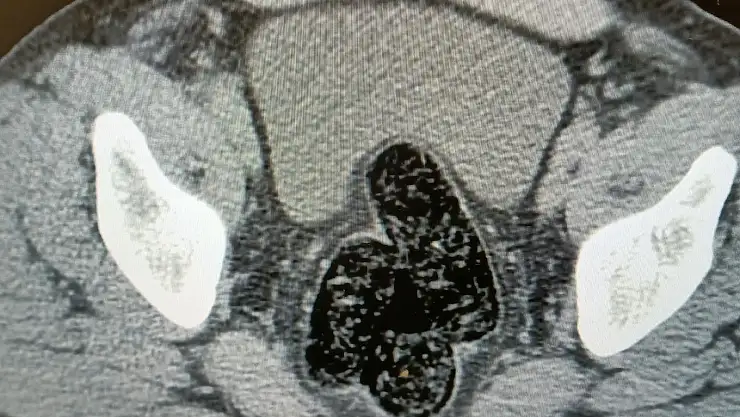

Ağrı'da İran uyruklu bir kişinin yapılan üst aramasında 10,17 gram, bağırsak ve makat kısmında ise 345,19 gram olmak üzere toplam 355.36 gram metamfetamin ele geçirildi

Ağrı Emniyet Müdürlüğü ekiplerince Bölge Trafik Şube Müdürlüğü önünde bulunan uygulama noktasında durdurulan ticari bir araç içerisinde yolculuk yapan İran uyruklu yabancı şahsın, yapılan üst aramasında, pantolonunun cebinden iki parça halinde şeffaf poşete sarılı vaziyette 10.17 gram metamfetamin ele geçirildi. Şahsın devam eden işlemlerinde gözlerindeki kızarıklık, yemek ihtiyacı istememesi ve aşırı tedirgin davranışlar sergilemesi üzerine şahısta yapılan iç beden muayenesinde, makat ve bağırsak kısmında uyuşturucu kapsülleri olduğu tespit edildi.

Doğal yöntemlerle şahsın makat ve bağırsaklarından 12 adet kapsül halinde toplam 345.19 gram metamfetamin çıkarılırken, şahsın üst aramasından ve iç beden muayenesinden toplam 355.36 gram metamfetamin ele geçirildi.